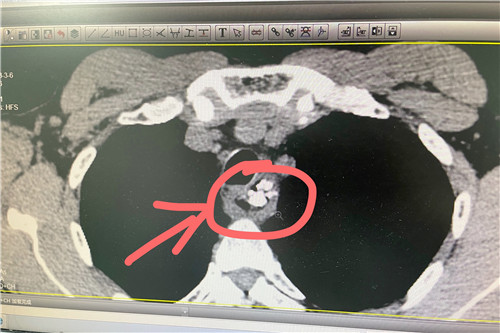

張爺爺誤咽帶有多根魚刺的魚脊椎骨,胸骨后疼痛梗阻2天,無法正常進(jìn)食。經(jīng)人介紹,碾轉(zhuǎn)來到石化醫(yī)院就診,經(jīng)食道CT加三維重建檢查,發(fā)現(xiàn)魚脊柱骨形狀不規(guī)則,且離主動(dòng)脈弓非常近,極有可能刺破主動(dòng)脈導(dǎo)致大出血。情況危急,是讓患者轉(zhuǎn)胸外科開胸?還是嘗試借助內(nèi)窺鏡取魚骨?

耳鼻咽喉頭頸外科團(tuán)隊(duì)迎難而上,借助內(nèi)窺鏡,用異物剪將魚脊椎骨剪成3段,分次取出。終于,這根長約4厘米、寬約4厘米的3節(jié)“非”樣魚刺被團(tuán)隊(duì)用“非常手段”巧妙取出,大家都舒了一口氣。